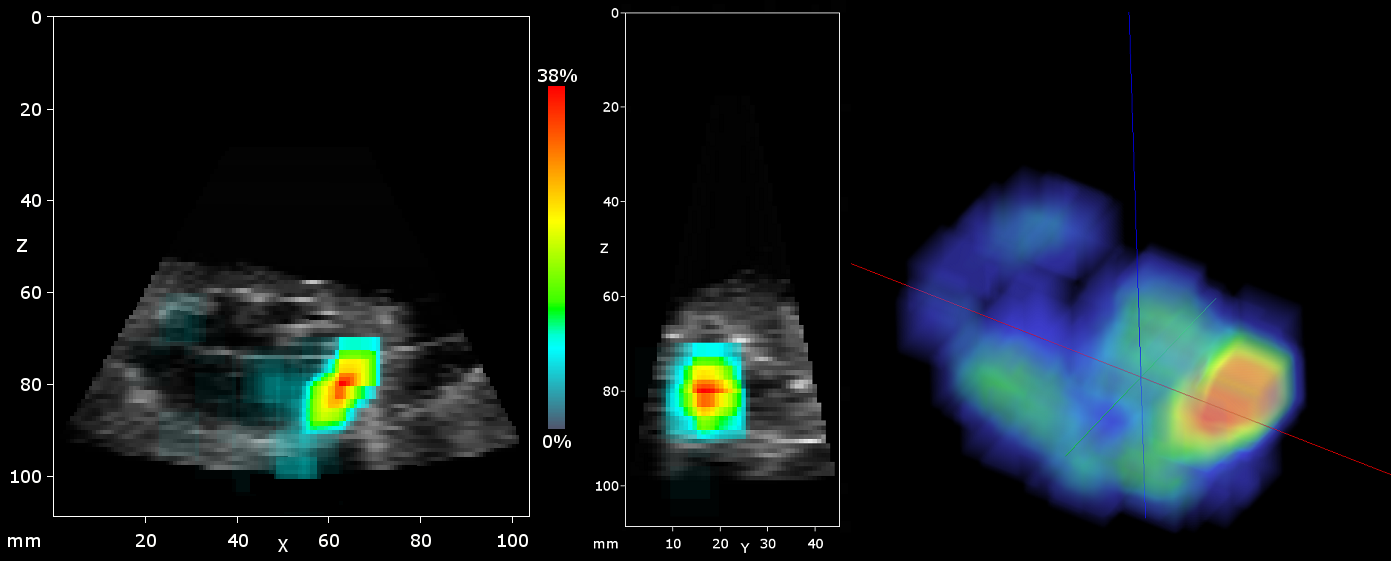

research:3dus:3dus_probmap.png

3dus_probmap.png